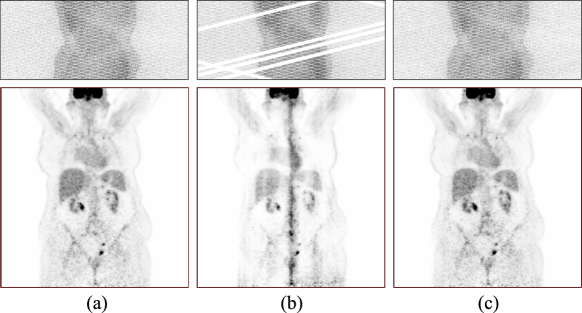

The combination of positron emission tomography and X-ray computed tomography (PET/CT) is used extensively both in both clinical and research environments where device up-time is a key operational metric for imaging organizations. During a PET scanner’s life, however, one or more block detectors in the imaging array will likely malfunction causing the system to lose coincidence events along the corresponding lines of response (LORs). As illustrated in Fig. 1, this creates gaps in the sinogram data which leads to artifacts and image degradation, as well as downtime for the scanner (Zito et al., , 2007; Elhami et al., , 2010; Voert et al., , 2016). This scenario is likely to become even more common as technological advances lead to scanners with longer axial fields-of-view such as the development and commercialization of whole-body PET scanners (Cherry et al., , 2018). This paper presents a deep learning based technique to mitigate single and multiple failed block detectors, while restoring reconstructed image quality.

Refer to caption

Figure 1: Illustration of the problem and the proposed solution: (top row) PET sinograms and (bottom row) reconstructed images; (a) standard clinical quality data; (b) effect of malfunctioning detector blocks; and (c) deep neural network restored data.